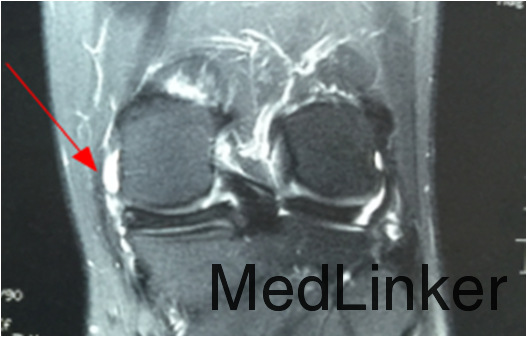

查体:左膝关节麦氏征(+),过屈试验(+),过屈位时内侧关节间隙触及囊肿。MRI检查提示:左膝内侧半月板损伤伴囊肿形成。

诊断:左膝内侧半月板损伤伴囊肿形成。行左膝关节镜检,内侧半月板周围囊肿切除+半月板修补术。术后开始行股四头肌肌力训练及踝泵训练,术后定期门诊复诊并行主被动康复训练。